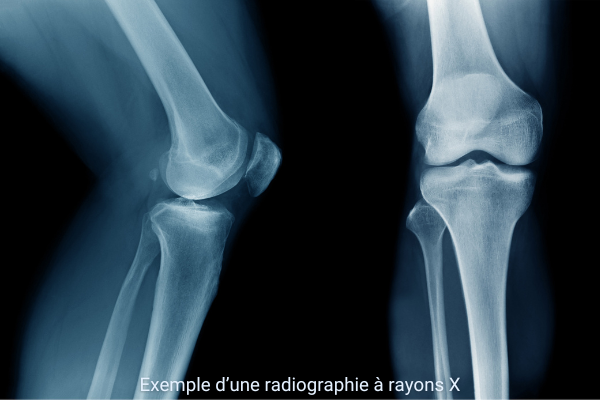

Principe et interprétation d’une radiographie

Lorsqu’un faisceau de rayons X traverse le corps, il est atténué de manière variable selon les tissus rencontrés. Cette atténuation dépend de trois facteurs principaux : le numéro atomique (Z) des éléments constitutifs du tissu, sa densité, mais aussi son épaisseur. Plus un tissu est épais, plus il absorbe de rayons X.

Ainsi, les os, riches en calcium et donc à fort numéro atomique, absorbent fortement le rayonnement et apparaissent blancs sur le cliché. Les tissus mous, constitués d’éléments plus légers comme le carbone, l’hydrogène ou l’oxygène, absorbent moins et apparaissent en nuances de gris. L’air, présent dans les poumons, absorbe très peu et se traduit par des zones sombres.

Les images obtenues révèlent parfois des signes pathologiques. Par exemple, dans une pneumonie, ce que l’on observe n’est pas directement « l’infection », mais des opacités pulmonaires, c’est-à-dire des zones blanches anormales dues à une inflammation ou à un comblement des alvéoles.

À retenir

L’absorption des rayons X dépend du numéro atomique, de la densité et de l’épaisseur des tissus. C’est cette absorption différentielle qui crée le contraste visible en radiographie.